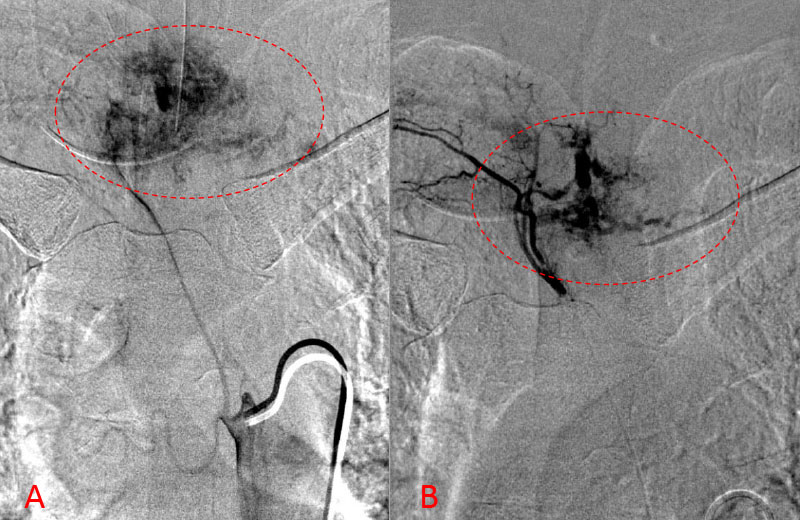

Spinal angiography showed a very hypervascular lesion fed predominantly by the right supreme intercostal artery (Figure 2. A, B).

Figure 2. A, B) Selective angiography of the right supreme intercostal artery demonstrates extensive hypervascularity of this aggressive T3 hemangioma.

No spinal artery contributions were found to arise from this right T1-T3 pedicle. Superselective WADA testing was performed with Brevital injected through the microcatheter, which failed to elicit changes in the intraoperative monitoring, confirming safety to proceed with devascularization of this pedicle and tumor. This was performed with 100-300 micron particles achieving an excellent devascularization (Figure 3. A, B).